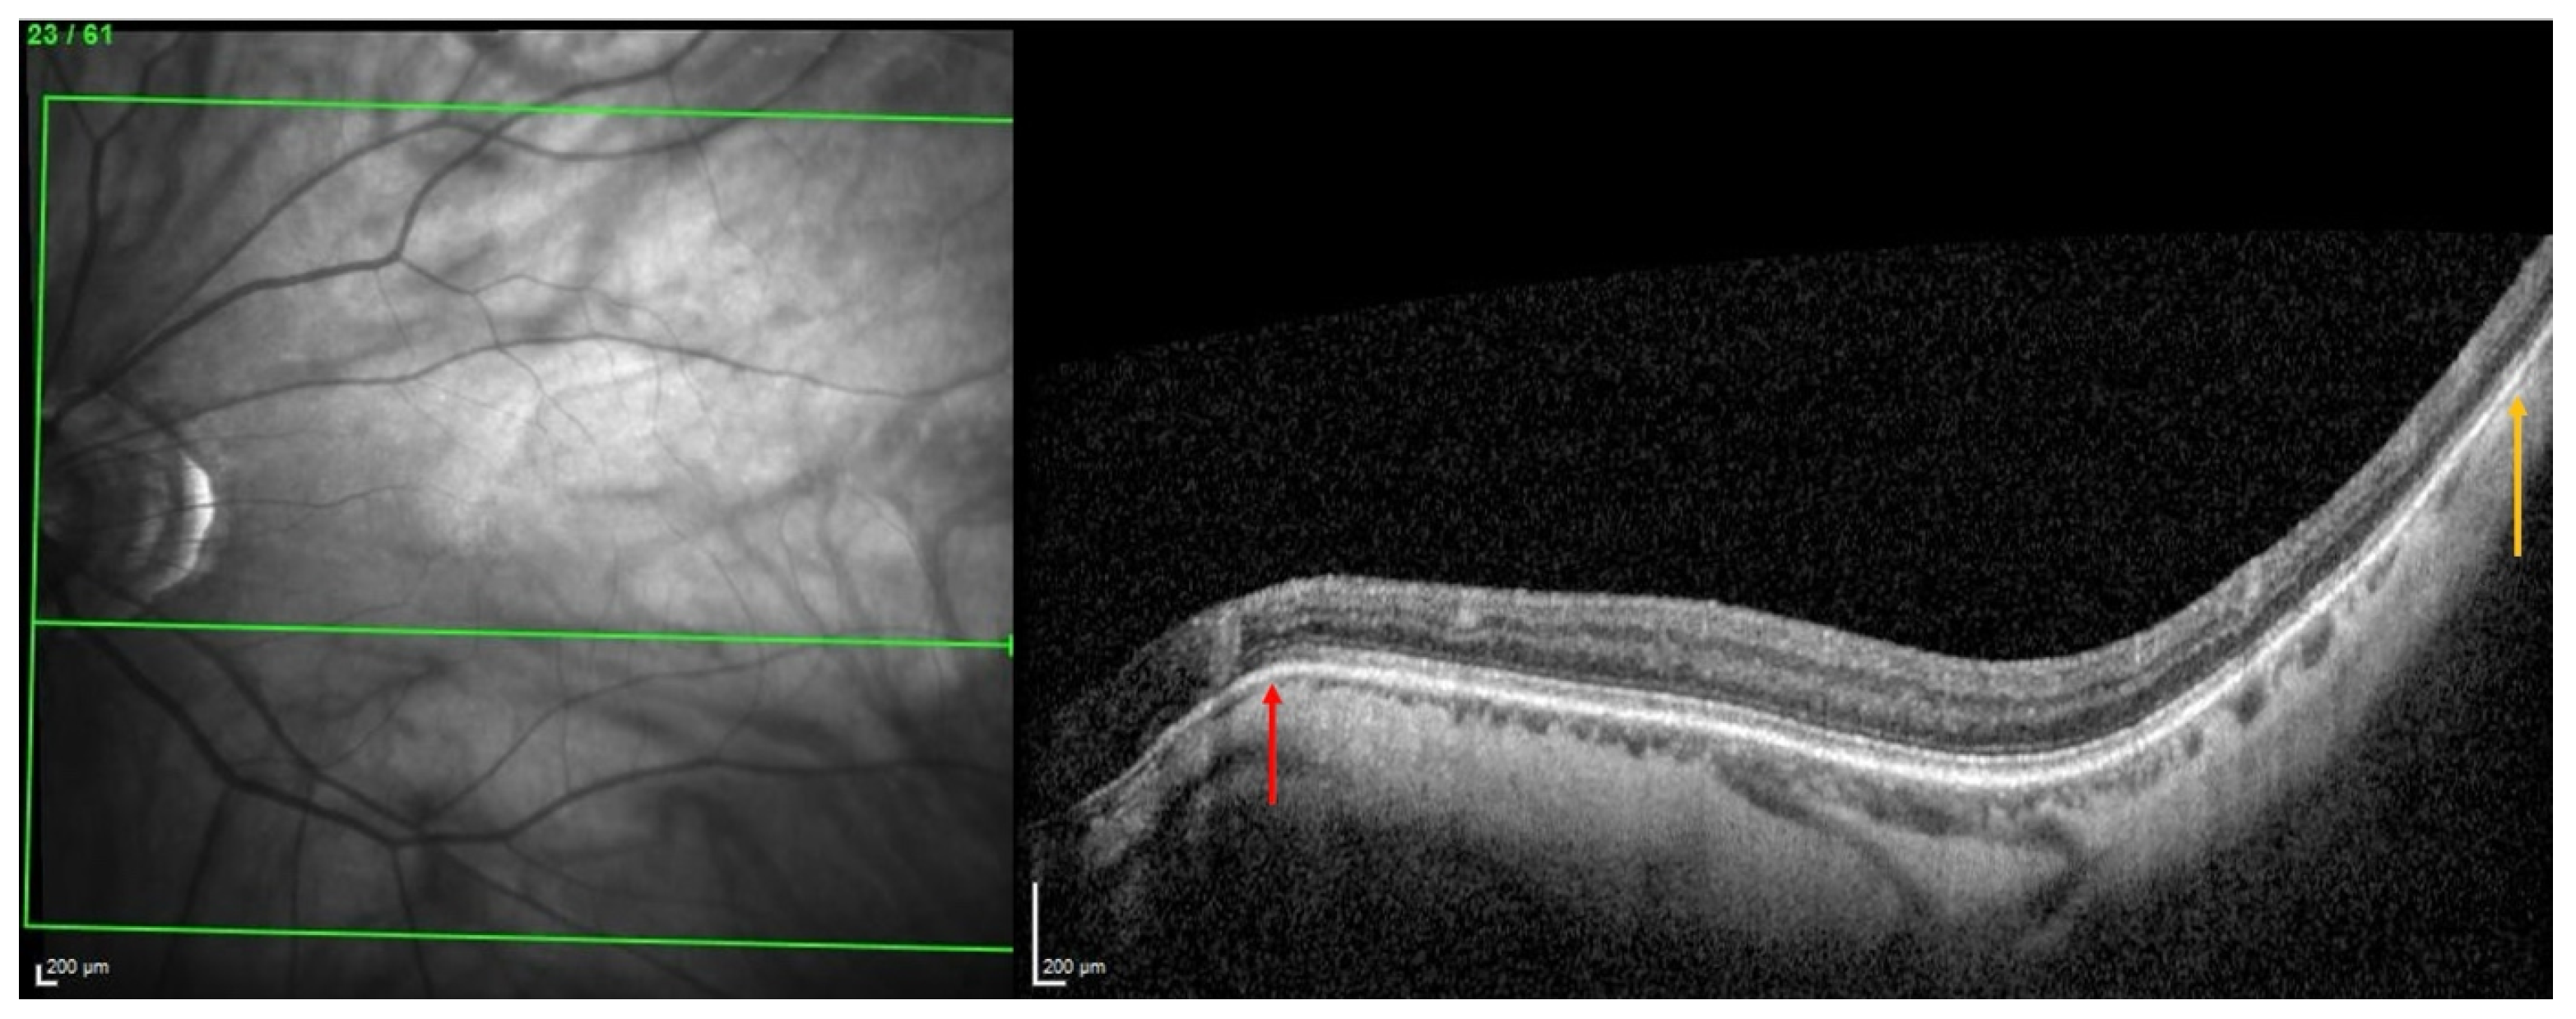

2.1.2. OCT Analysis

- A search for choroidal thinning in 3 locations in the temporal part of the posterior pole.

- Measurement of the choroidal thinning and distance from fovea to thinning.